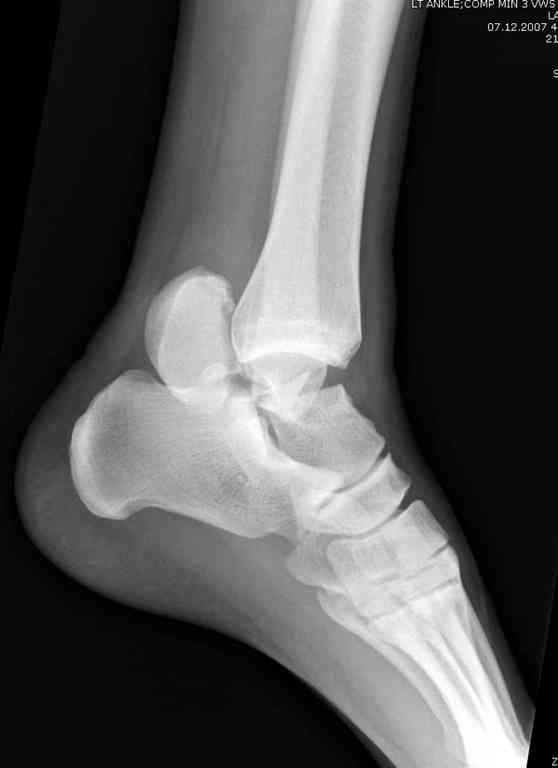

Здесь на фото примеры:

Переломовывих тарана с повреждением медиальной стороны. Через 4 часа после поступления проведена репозиция и фиксация тарана после Irrigation&Debridment. Частичное несращение медиальной лодыжки не беспокоит, вернулся к активному образу жизни. Полная нагрузка разрешена через 11 недель. Финальные снимки через 11 месяцев.